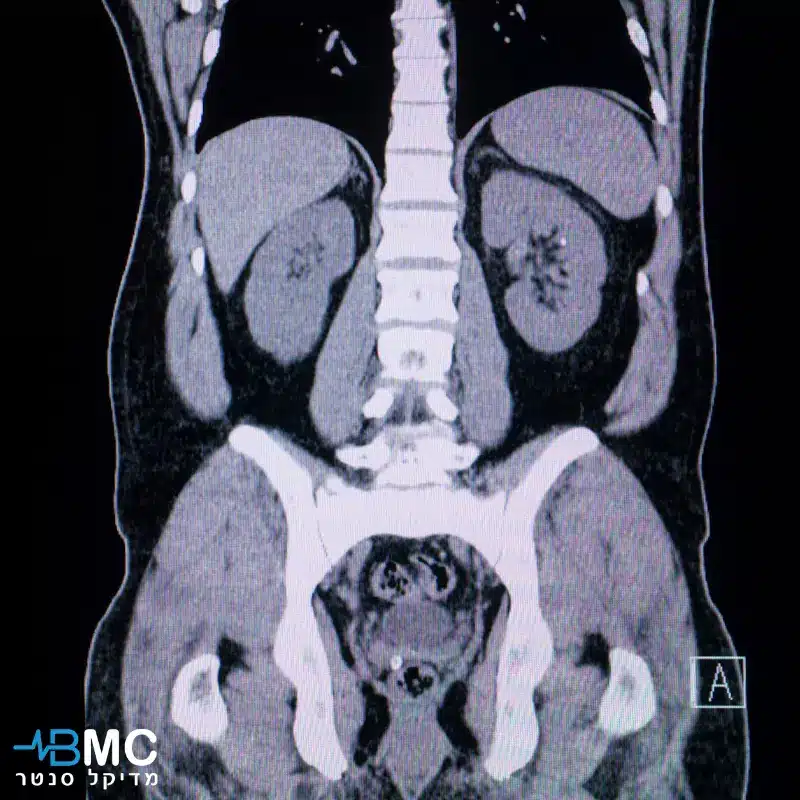

על פי הסוגים של הדי הקול, הרדיולוג, המתמחה בפענוח התמונות, יכול להבחין בין רקמה תקינה לבין רקמה שיש בה חריגה רפואית. אולטרסאונד אשכים, בודק באופן ספציפי את האשכים, הנמצאים בתוך שק האשכים.

אולטרסאונד מספק תמונות ברורות ומפורטות של האשכים, המאפשרות לרופא לאבחן בצורה מדויקת מגוון רחב של מצבים, כמו גידולים- זיהוי מוקדם של גידולים סרטניים או שפירים באשכים; ציסטות- זיהוי של שקיות מלאות נוזל באשכים; דלקות - זיהוי של דלקות באשכים או בשק האשכים; בעיות בזרימת הדם- זיהוי של חסימות או הפרעות אחרות בזרימת הדם לאשכים.